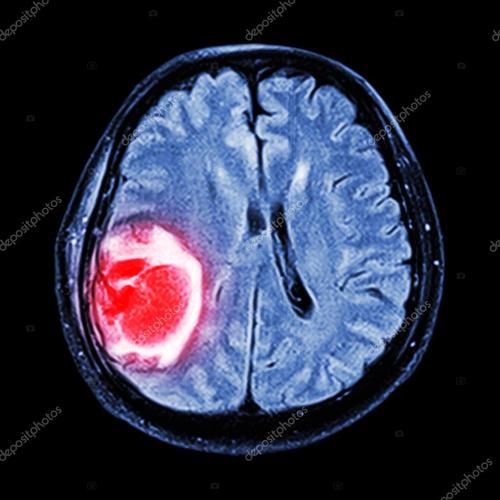

腦腫瘤可以治療,顱內(nèi)腫瘤有良性的腫瘤和惡性腫瘤之分。良性的腫瘤一般做完手術(shù)就可以治愈了。如果是惡性的話,需要術(shù)后要進(jìn)行輔助放化療。

目前,國(guó)內(nèi)外對(duì)腦腫瘤的治療多采用手術(shù),化療、放療等,但大多難以治愈,惡性腫瘤病程短,發(fā)展快,根據(jù)惡性程度高低手術(shù)切除的多少或放化療的敏感度,復(fù)發(fā)有早有晚,生長(zhǎng)在腦干、丘腦等重要部位的腫瘤難以手術(shù)或不能手術(shù)。

X刀,放射等治療后的腫瘤可有縮小或短時(shí)間內(nèi)控制增長(zhǎng)以后瘤體不再生長(zhǎng)、再?gòu)?fù)發(fā),良性腫瘤病程較長(zhǎng),生長(zhǎng)緩慢,手術(shù)完全切除的不易復(fù)發(fā),但生長(zhǎng)在腦干等重要部位的腦瘤手術(shù)只能部分或大部分切除,手術(shù)后瘤體還會(huì)再?gòu)?fù)發(fā)、再生長(zhǎng)、顱內(nèi)惡性腫瘤手術(shù)后放、化療平均存活率不足一年。

偏良性的膠質(zhì)瘤,垂體瘤、顱咽管瘤、膽脂瘤等顱內(nèi)良性腫瘤手術(shù)不易切除干凈,γ刀、X刀、放射治療并不可能徹底殺死腫瘤,因此大部分患者手術(shù)后仍然會(huì)再?gòu)?fù)發(fā)。